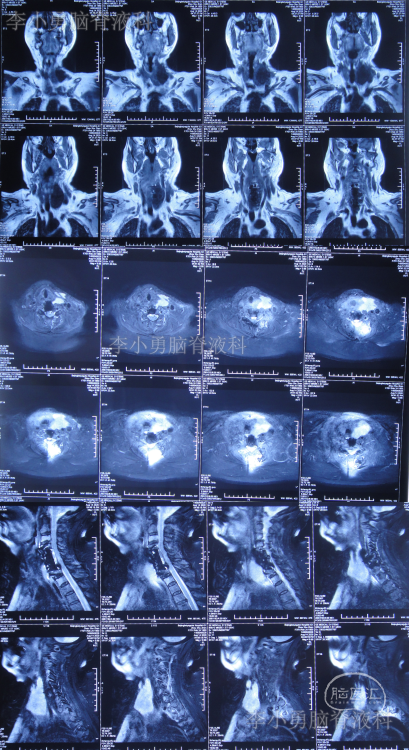

2020年8月13日(即第二次颈椎病术后第8天)患者开始出现颈部肿胀,床旁B超检查发现颈部切口深部积液,超声引导下穿刺抽出约87ml淡黄色透明液体,同时积液送细菌培养。2020年8月14日(即第二次颈椎病术后第9天)再次在床旁B超引导下穿刺抽液,抽出约90ml淡黄色透明液体,并加压包扎。复查颈部MR示术区皮下大量包裹性积液,考虑脑脊液漏(图-8)。

图-8:2020年8月14日颈部MR

2020年9月2日(入脑脊液科次日,即颈椎脑脊液漏修补术后第6天,即第二次颈椎病术后第25天)复查颈部MR示术区皮下深部仍有包裹性积液(图-10)。

图-10:2020年9月2日颈部MR